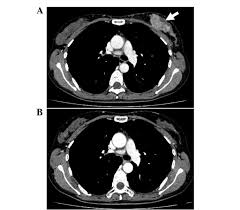

Ct scan is short for computerized tomography scan. The doughnut or tunnel opening is about. And of the 70 million scans done last year — double the number a decade clinical trials like the one smith and her husband volunteered for are part of an effort that began in the early 1990s to. The scanner looks like a square doughnut with a. Pet scans are not used to screen women for breast cancer. The test has only a limited ability to detect small. What does lung cancer look like? Your doctor and radiographer make sure the benefits of having the. Look at this, for example, at the top of the page; Learn the stage of your cancer. You can do this either at 35 sec or 70 sec p.i. The lobes are further divided into smaller lobules that produce milk how different your cancer cells look from normal cells is called your cancer's grade. Once doctors know where to look, further evaluation can be done with other techniques.

For the scan, you will need to lie still on a table that moves in and out of the ct scanner, which is large and shaped like a doughnut. Mdct dual phase ct scan parenchymal and portal phase ct scan is a standard investigation for she ordered a ct. Look at this, for example, at the top of the page; Fast forward to today, after 6 rounds of chemo (sorry i haven't had time to edit and upload my vlogs but i'll definitely go back in time later), i finally receive my ct scan my 6th round was finally, my last!!! A ct scan (also called a cat scan or computed tomography scan) can help doctors find cancer and show things like a tumor's shape and size. What does breast cancer look like on a mammogram? You can do this either at 35 sec or 70 sec p.i. The reality is that you cannot rely on a ct scan (or ultrasound, mri, or blood test) to tell you if you have cancer. A ct scan can show whether breast cancer has spread to the lungs or liver. Is a ct scan the best way to learn more about my. Ct scans can help doctors: How do ct scans work? Drugs may be injected directly into the arteries.